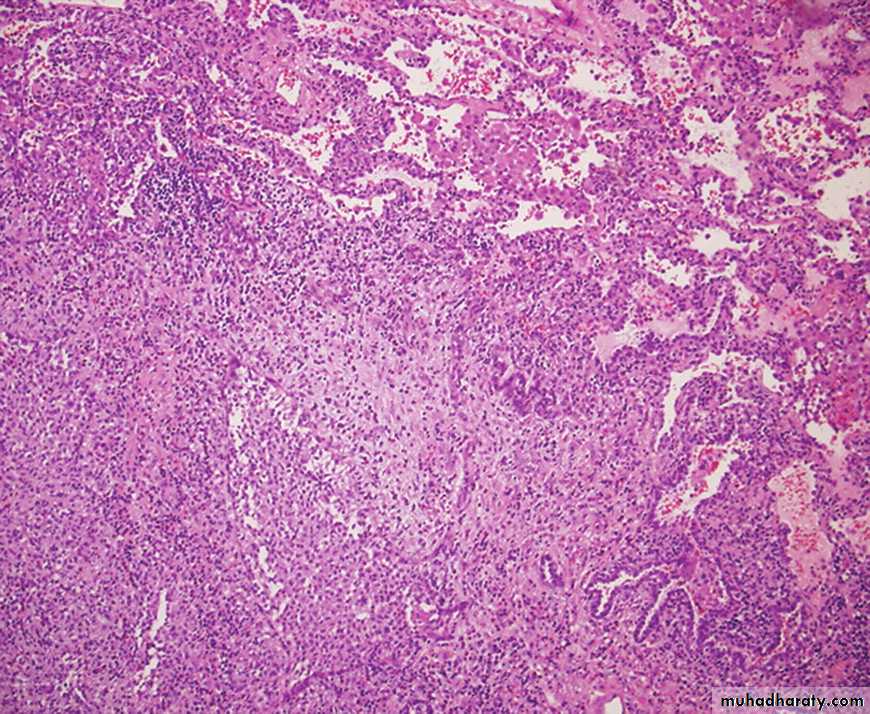

IPF is defined as a progressive fibrosing interstitial pneumonia of unknown cause, occurring in adults and associated with the histological or radiological pattern of usual interstitial pneumonia (UIP). Previously known as cryptogenic fibrosing alveolitisThere is some role of viral exposure e.g. EBV, occupational dust e.g. metal or wood, drugs e.g. antidepressant or GERD. There is a strong association with cigarette smoking.

Abnormal chest X-ray at presentation with lower zone bi-basal reticular and reticulonodular opacities. 'honeycomb' appearance in advanced disease.

HRCT may be diagnostic, demonstrating a patchy, predominantly peripheral, subpleural and basal reticular pattern with subpleural cysts (honeycombing).